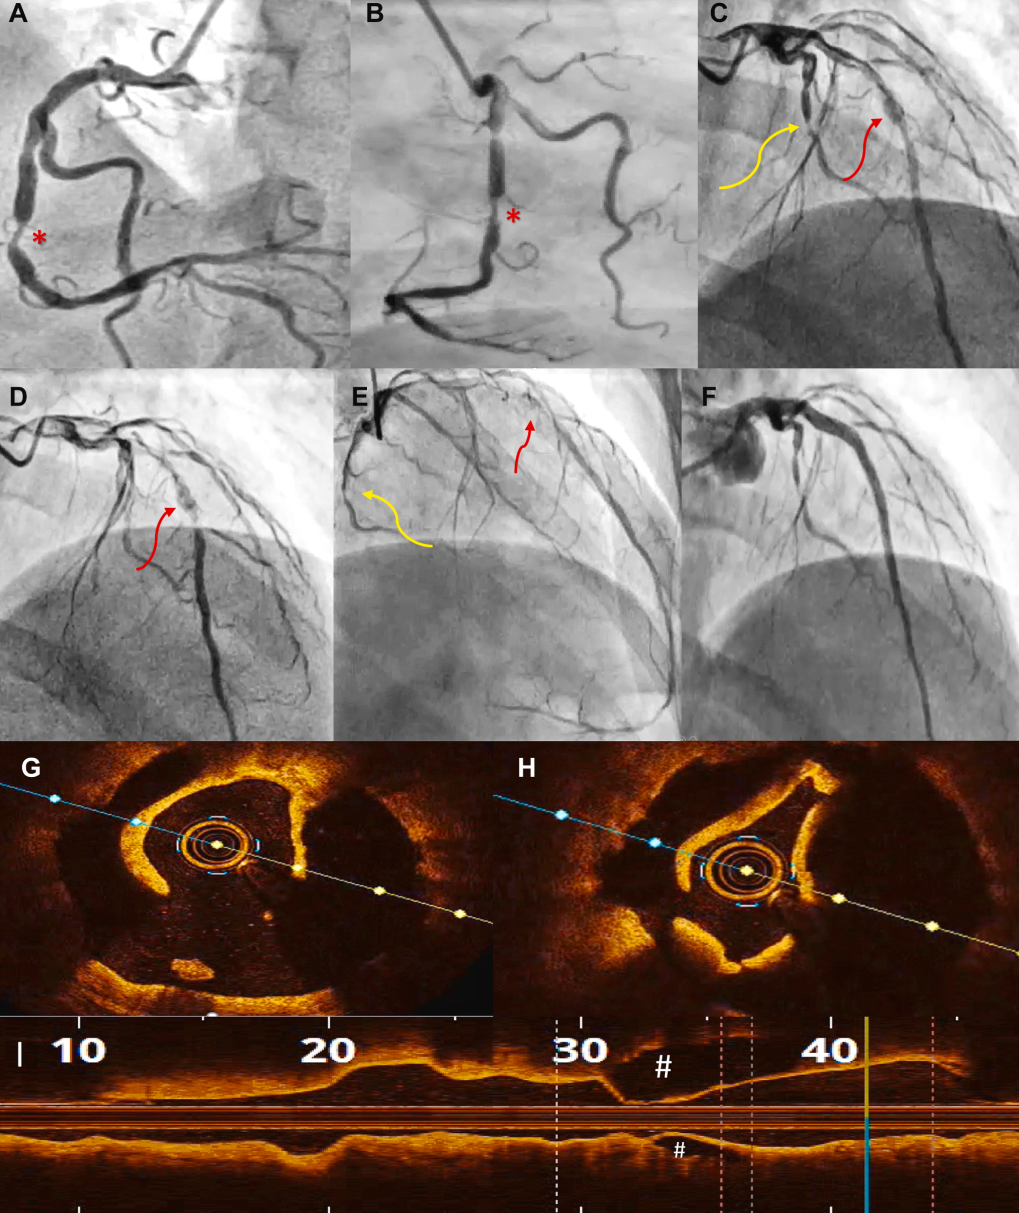

图1 病例1:血管造影

2018年在另一家中心,(A)右冠状动脉(RCA)疑似自发性冠状动脉夹层(SCAD)。(B)左回旋支动脉(LCX)和(C)可能遗漏的左前降支动脉(LAD)SCAD。2024年在我们中心,被解读为(D)近段 LAD 的 SCAD 以及(E)粗大非优势 LCX 的广泛 SCAD(红色箭头)并累及主要钝缘支(OMM),(F 和 G)右冠状动脉(RCA)自开口至后降支(PDA)和后左室支(PLV)的广泛 SCAD(红色箭头)。

2024年,复查造影显示疑似SCAD累及近端左前降支(LAD)、近端LCX延伸至钝缘支,以及从RCA开口至左室后支和后降支(图1D至1G)。患者左心室射血分数(LVEF)下降至35%-40%。

鉴于复杂的解剖结构和降低的LVEF,在IVUS引导下对RCA进行了经皮冠状动脉介入治疗(PCI)。然而,IVUS未能区分SCAD与血栓(图2)。

图2 病例1:RCA 经皮冠状动脉介入治疗(PCI)前后的血管内超声图像

(A)从 RCA 近端到 PDA 可见多个血液充盈的管腔(黄色箭头)。(B)经皮冠状动脉介入治疗(PCI)后血管内超声图像显示支架膨胀良好,以及 PDA 远端节段健康。

第一个支架被放置在远端,主要在健康节段,以封闭广泛的 SCAD 防止其扩展并封闭假腔(近端)。支架植入后观察到后左室支假腔闭合,这可能是由于上述作用所致。

案例三:为造影表现不明确的STEMI 患者明确诊断

一位48岁男性STEMI患者,其LAD的造影结果不明确(血栓性闭塞或1型SCAD)(图6A至6F),且TIMI血流2级;同时,RCA中段和钝缘支分支疑似3型SCAD。

图6 病例3:患者血管造影和左前降支(LAD) OCT 图像

(A)左前斜头位视图显示右冠状动脉(RCA)中段疑似3型 SCAD(∗)。(B)右前斜位视图显示右冠状动脉(RCA)疑似 SCAD(∗)(C-E)。左前降支(LAD)中段可见可疑充盈缺损(1型 SCAD/再通血栓)伴有造影剂延迟清除(红色箭头),以及左回旋支(LCX)/钝缘支(OM)疑似3型 SCAD(黄色箭头)(F)。左前降支(LAD)最终 PCI 结果(G 和 H)。左前降支(LAD)管腔被向内推挤;假腔用 # 标示(I)。OCT的 L 模式:真腔被假腔(#)向内推挤。

鉴于诊断不确定性,对LAD进行OCT检查(图6G 至6I),显示了真腔被壁内血肿向内推移,从而确诊了SCAD。随即使用1:1切割球囊和药物洗脱支架进行了PCI,实现了TIMI血流3级。